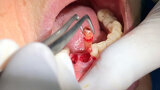

Figs. 7. Remoción delicada de los restos radiculares y comproba

Figs. 8. Remoción delicada de los restos radiculares y comproba